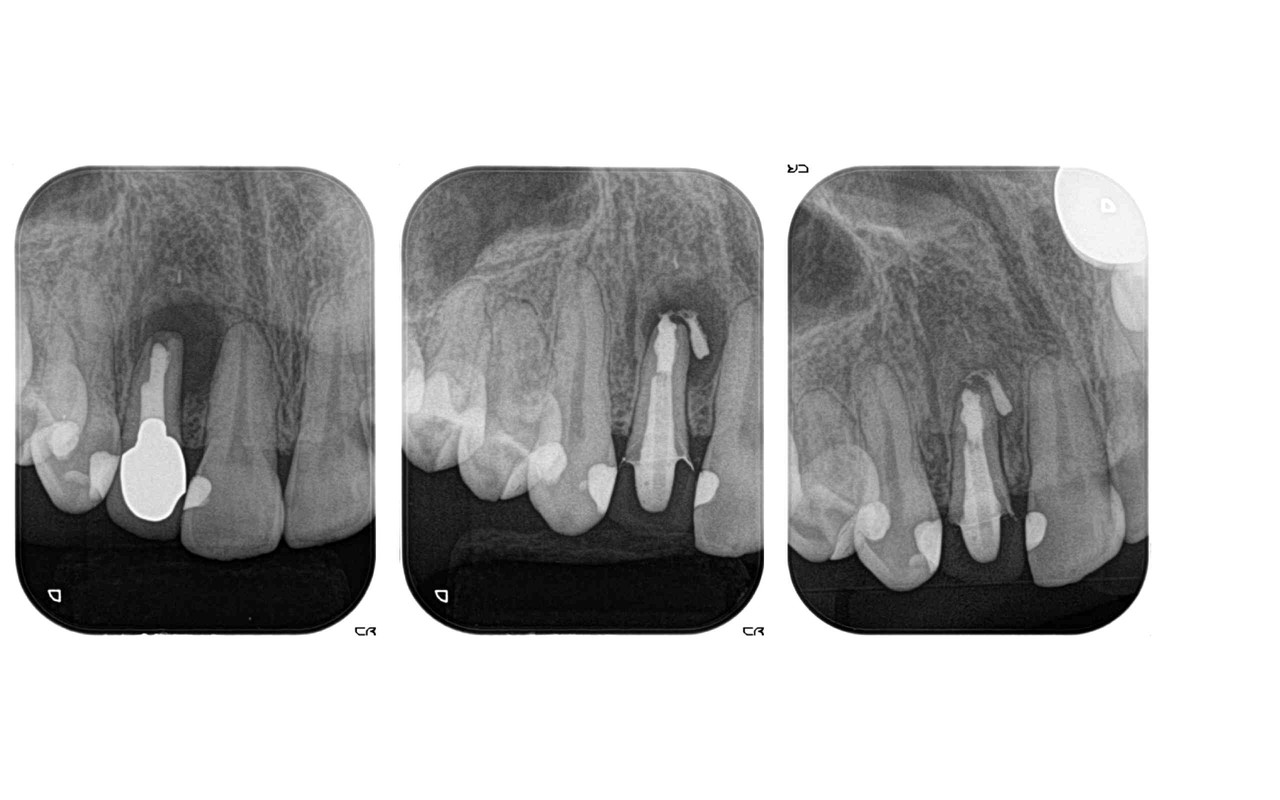

歯の根っこの先に炎症があるため歯を抜くと言われた方の根っこの再治療例です.左側が最初の状態です.根っこの先に骨が吸収して黒い丸い像が見えますが,根っこの中を消毒する事で根っこの先の黒い丸が右側の写真では無くなっています.炎症が無くなっていますので歯を抜かずにそのまま残す事ができました.

歯を抜く前に残せないか確認するためにCTを撮影する場合があります.

歯を抜くかあるいは残せるかの判断は最終的にCTを取ることで直接目で見えない部分までミクロ単位で確認することができます。歯の周囲の状況が3次元的に確認できるため、今まで想像や経験で判断していた部分がしっかりと確認できることも増えました。

歯の根っこが炎症を起こして根っこの先の骨が吸収してしまっている場合、抜いてインプラント治療を勧められる事があります.

歯を抜かずに根っこの神経の治療を行う事で、歯を保存する事が出来る場合があります.

歯を抜かずに根っこの神経の治療を行う事で、歯を保存する事が出来る場合があります.

最近、歯を抜くかどうするかと言う基準はだんだんと細かい基準になって来ています.歯の根っこの先の炎症や中程度の歯周病、中程度の歯のヒビ、虫歯がある程度深い場合でも歯を残せる可能性が高くなって来ています.